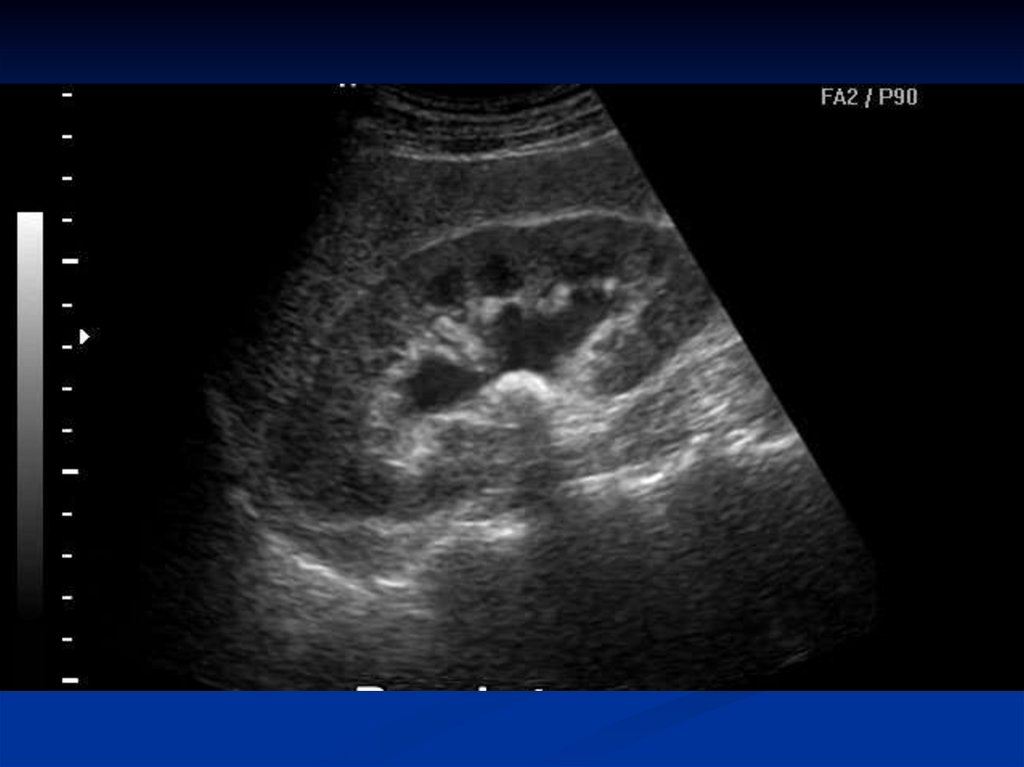

УЗИ почек и мочевого пузыря. Его преимущества неоспоримы:

- высокая информативность: определять параметры, количество, расположение (в мочеточнике, почечных лоханках, чашечках), а также оценивать состояние почечной ткани и наличие симптомов затрудненного мочеотделения (гидронефроз).

Что может увидеть врач на мониторе?

Эхогенные включения |

Камни в почках на УЗИ смотрятся как белые (гиперэхогенные) кристаллы с эффектом акустической эхотени позади себя. Размер и форма включения также оцениваются. |

|

Состояние почечной паренхимы |

Оценить толщину и структуру почечной ткани, выявить возможные воспалительные изменения или рубцы |

Расширение чашечно-лоханочной системы (гидронефроз) |

При наличии камня, блокирующего отток мочи, чашечки и лоханки почки расширяются, что также видно на мониторе. Это является важным признаком, указывающим на необходимость вмешательства. |

Состояние мочевого пузыря |

Видны микролиты, а также остаточный объем после мочеиспускания |

Несмотря на высокую информативность, УЗИ имеет некоторые ограничения. Микролиты, расположенные в узких участках мочеточника или за костными структурами, будут менее заметны. В таких случаях потребуются доп.исследования.